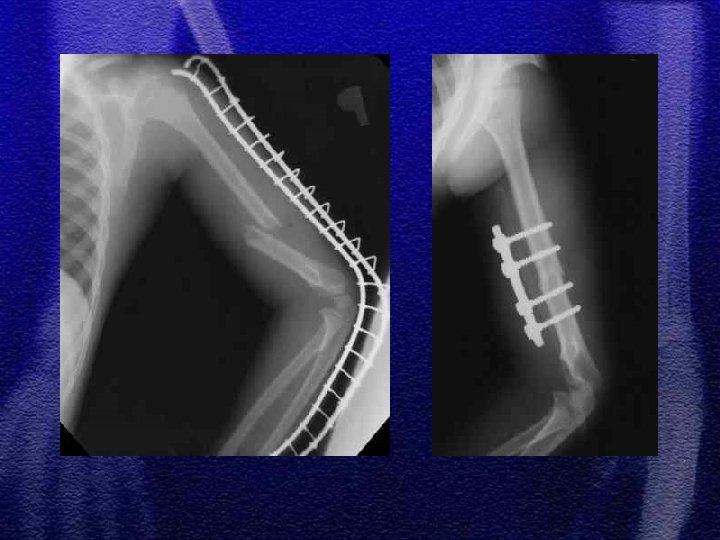

§ Do 4 roku życia leczenie wyłącznie zachowawczewyciąg plastrowy lub szkieletowy w zależności od wieku § Większość złamań do 10 r. ż. - wyciąg szkieletowy ok. 3 tyg. , a następnie gips biodrowy od 3 do 6 tygodni w zależności od wieku § Leczenie operacyjne rozważa się po 10 roku życia a metody zespolenia to: Zespol, pręty Endera, Rusha, stabilizatory zewnętrzne